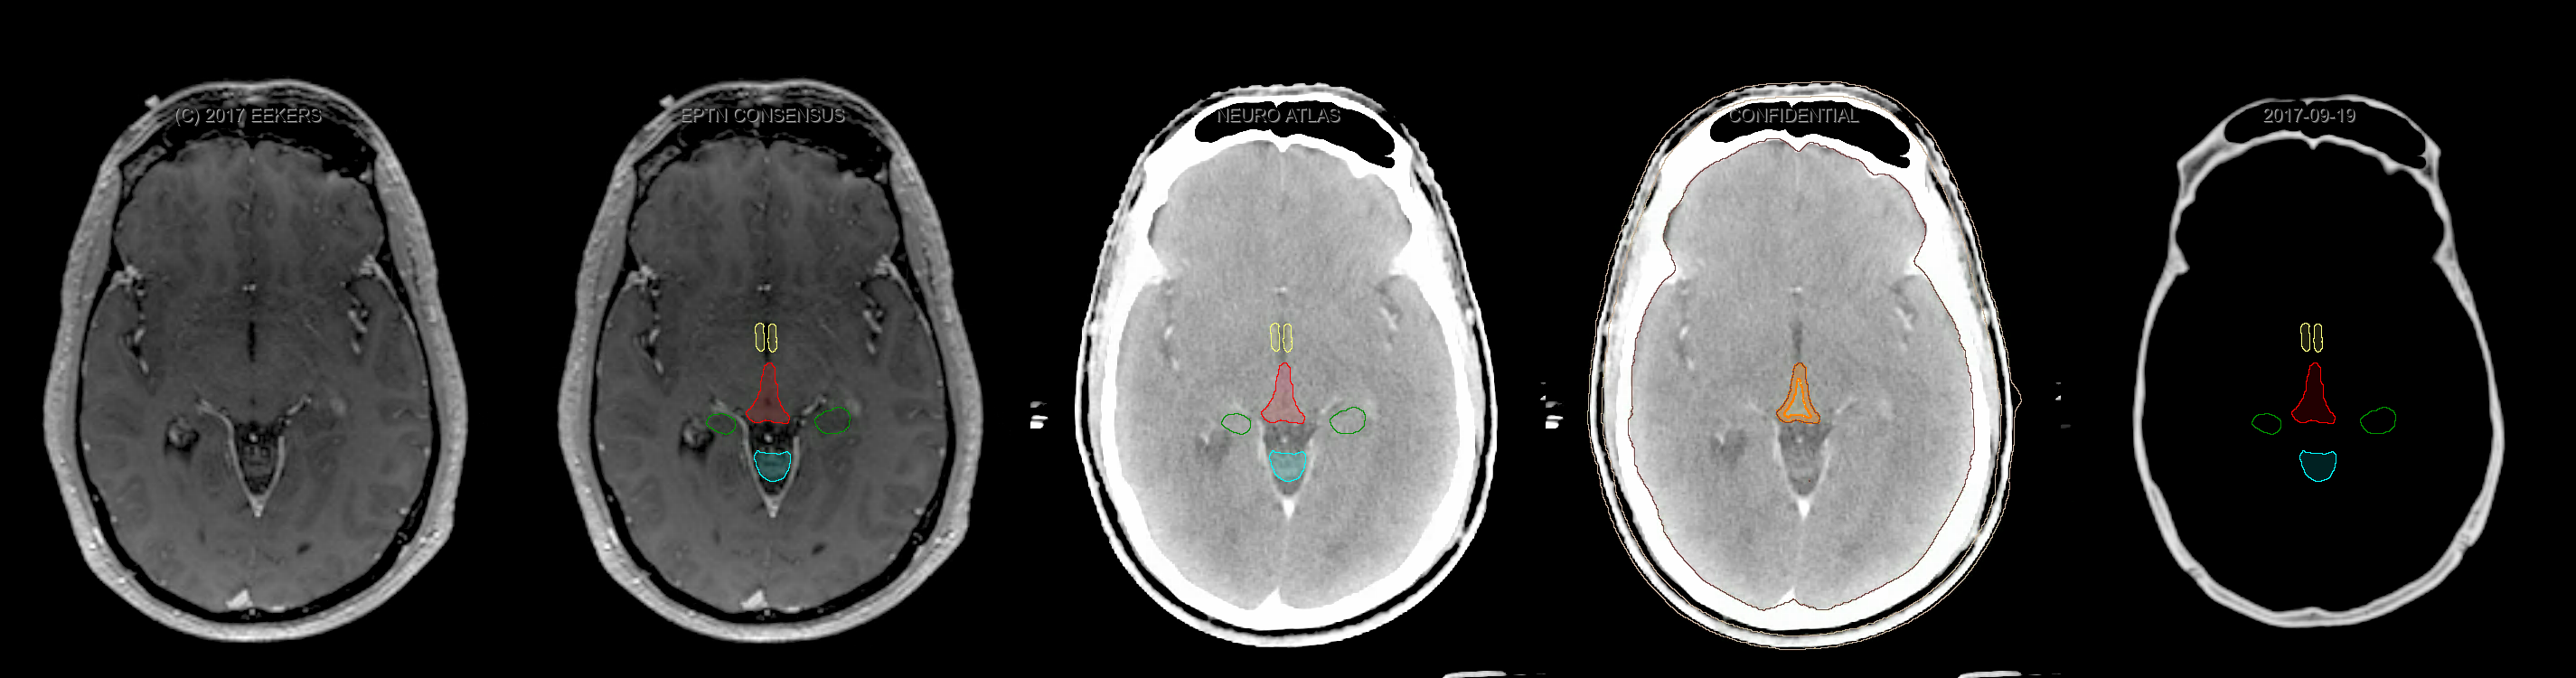

Eekers et al. have published an international neurological atlas for contouring of organs at risk in consensus with the European Particle Therapy Network (EPTN). The purpose of this consensus atlas is to decrease inter- and intra-observer variability in delineating OARs relevant for neuro-oncology. We propose this atlas is used in photon and particle therapy in order to derive consistent dosimetric data. When required this atlas will be updated according to new insights.

Included are all OARs known to be relevant for radiation-induced toxicity in neuro-oncology: brain, brainstem, cochlea, vestibulum & semicircular canals, cornea, lens, retina, lacrimal gland, optic nerve, chiasm, pituitary, hippocampus and skin. A new OAR relevant for neuro-cognition, the posterior cerebellum is also included.

Three-dimensional delineation of the fifteen consensus OARs for neuro-oncology are shown on CT and 3 Tesla (3T) MR images (slice thickness 1 mm with intravenous contrast agent). All are presented in transversal, sagittal and coronal view.

From left to right: MR without structures, MR with structures, CT (WW/WL 120/40) with structures, CT (WW/WL 120/40) with Brain and Brainstem Surface, CT (WW/WL 1500/120)with structures